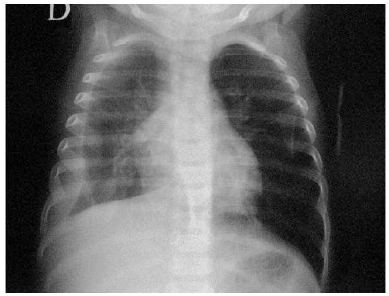

Uma criança de dois anos apresenta há três dias tosse, coriza e febre alta. Nas últimas 24 horas, passou a ficar mais prostrada e taquidispneica. Foi solicitada uma radiografia de tórax, que apresentou o seguinte resultado:

Com base no resultado do exame, deve-se proceder da seguinte forma: